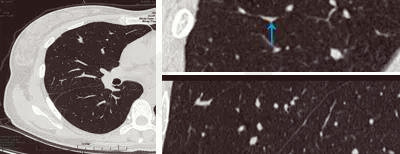

無(wú)獨(dú)有偶,34歲的張女士在一次體檢中發(fā)現(xiàn)肺部有肺磨玻璃影,在結(jié)節(jié)的性質(zhì)沒(méi)有確定前,她焦慮萬(wàn)分,“我沒(méi)有咳嗽又沒(méi)有發(fā)燒怎么會(huì)有肺結(jié)節(jié)呢?”“肺磨玻璃結(jié)節(jié)是不是就是肺癌?”“要手術(shù)嗎?” ……帶著一連串疑問(wèn),她來(lái)到肺結(jié)節(jié)影像??崎T(mén)診就診,經(jīng)影像專科醫(yī)生的檢查識(shí)別,明確診斷為斜裂局部胸膜增厚所致假病灶,從而徹底解除了張女士的擔(dān)憂。

局部胸膜增厚